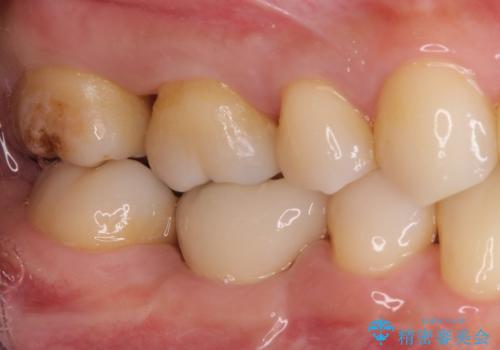

むし歯の治療。ゴールドインレーによる修復

ゴールドインレーは適合が良く、割れることもないため、長期的に安定した治療法となります。

- 定期健診にてむし歯を認めたためゴールドインレーにて治療を行いました。